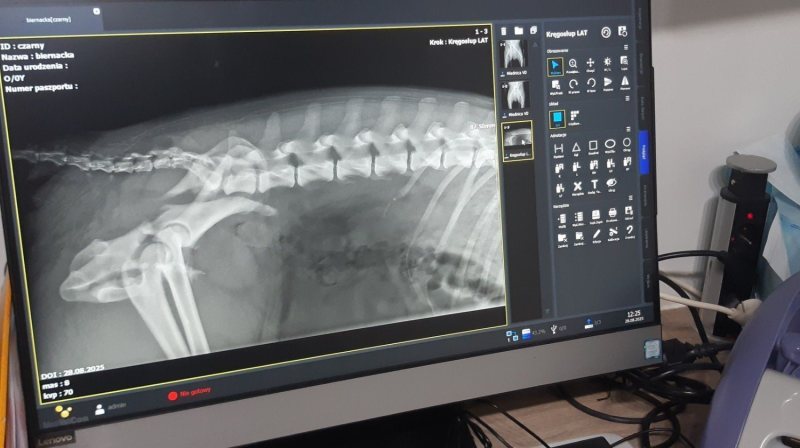

Ile dobra i miłości może pomieścić ludzkie serce? Mieszkańcy Świętajna pokazują, że ich serce dla zwierząt nie ma granic. Właśnie walczą o uratowanie potrąconego przez auto labradora - Czarka. Pies ma złamaną miednicę. Mimo to Stowarzyszenie Kundel Bury ze Świętajna zebrało ponad 6 tys. zł na operację, która da mu szansę na normalne życie i powrót do zdrowia. Teraz szukają dla psa nowego domu - jeśli nie na czas rehabilitacji, to chociaż po...

Czarek, to czarnego umaszczenia pies w typie labradora. Ma może 7 lat. W nocy z środy na czwartek znaleźli go mieszkańcy pobliskiego domu, leżał w rowie obok ich bramy. Ewidentnie został potrącony przez jakiś pojazd… więcej na temat tej sprawy w papierowym wydaniu „Tygodnika Szczytno”: